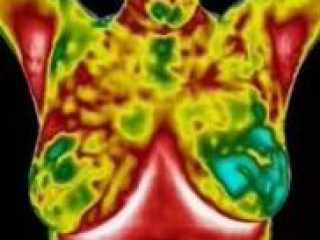

La thermographie est un outil une technique de dépistage précoce particulièrement efficace pour les seins, puisqu’elle permet de détecter d’éventuelles anomalies (telles que tumeur, cancer, kyste ou mastite, …) avant même l’apparition d’une lésion qui pourrait être détectée par d’autres moyens.

Le principe est simple: dans les tissus pré-cancéreux et autour d’une inflammation en développement, les vaisseaux sanguins ont une activité plus élevée que dans un sein normal. Cela produit une chaleur que nous allons mesurer avec une infime précision, à l’aide d’une caméra infrarouge à la pointe de la technologie moderne.